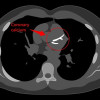

Mohon ijin konsul pasien Perempuan, 74 th

Keluhan: sesak sejak 1 hari SMRS, nyeri ulu hati (+), mual (+), muntah (-). Kedua kaki bengkak sejak 2 hari SMRS. Batuk, demam, nyeri dada khas.

Makan minum menurun, BAK dan BAB seperti biasa.

RPD disangkal, Riw. Obat di sangkal